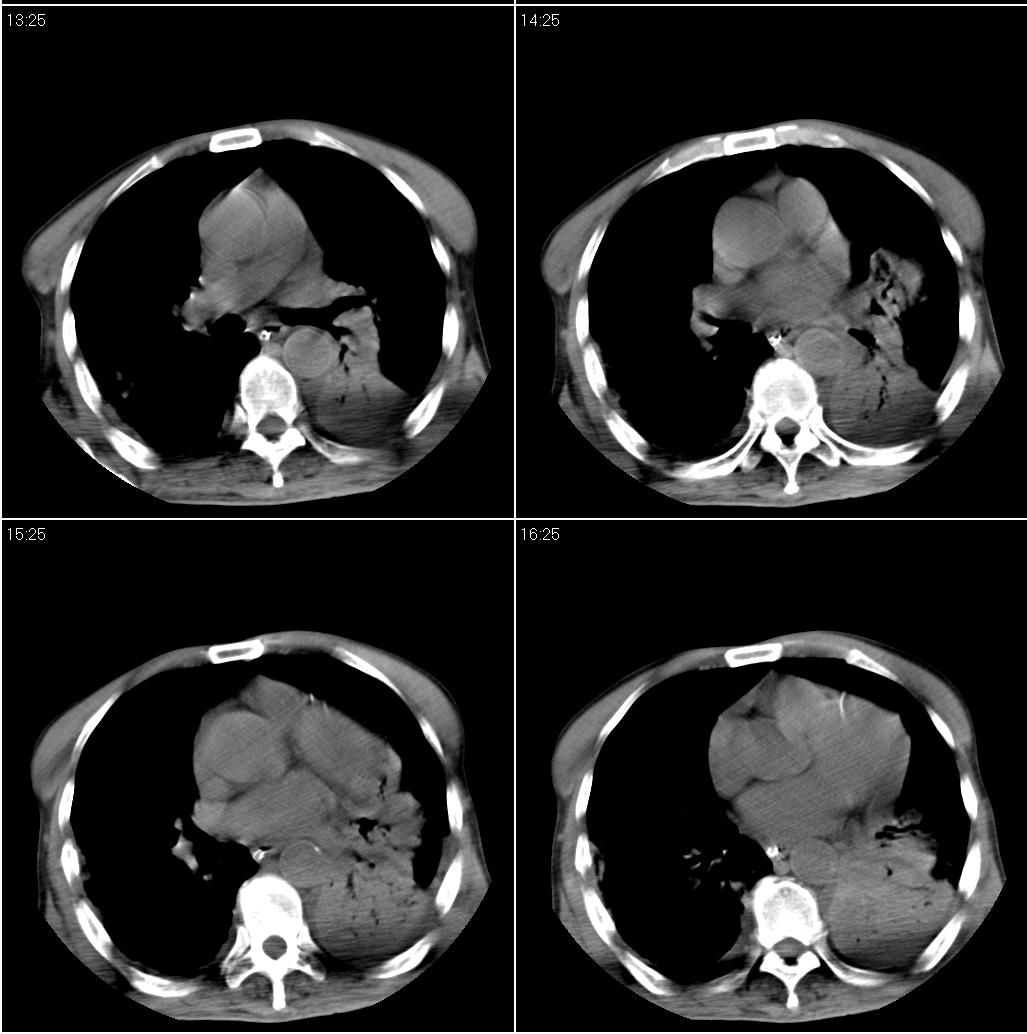

男性,65岁。因外伤来诊。该患者因脑外伤住院。以下是今天的dr和ct:

一周前胸片无异常,不考虑肿瘤,现x片及ct表现应与外伤有关,考虑左侧外伤性膈疝,并左下肺不张。右肺挫裂伤。少量胸水。

一周前胸片无异常,不考虑肿瘤,现x片及ct表现应与外伤有关,考虑左侧外伤性膈疝,并左下肺不张。右肺挫裂伤。少量胸水。支持

1 外伤性左侧膈疝、胸腔积液致左肺下叶不张 2右肺挫伤

右侧第7肋骨腋段骨折并右肺挫伤;左侧膈疝并肺不张。